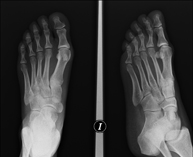

- RX Extremidades

Técnica mediante la cual, utilizando rayos X, se obtienen imágenes del interior de las extremidades para su estudio, especialmente de los huesos. Indicaciones: traumatismo, infecciones articulares. - RX Artrografía

Técnica mediante la cual, utilizando rayos X, se obtienen imágenes de la totalidad de ambas extremidades inferiores para su estudio, valorando especialmente la presencia de dismetrías entre ambas. - RX Extremidades

Técnica mediante la cual, utilizando rayos X, se obtienen imágenes de ambas extremidades para su estudio. - RX Caderas